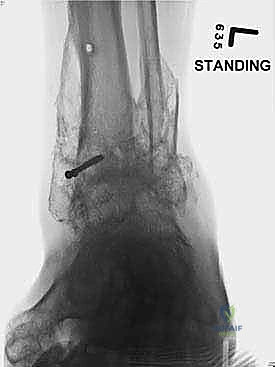

- الأشعة السينية أثناء الوقوف (Weight-bearing X-rays): هي الفحص الذهبي والأهم. يجب أن تؤخذ الأشعة والمريض واقف لتحمل الوزن. تظهر الأشعة تضيق المسافة المفصلية (دليل على فقدان الغضروف)، وجود نتوءات عظمية، تصلب العظم، وأي انحراف في محور المفصل.

- التصوير المقطعي المحوسب (CT Scan): يطلبه الدكتور هطيف لتقييم جودة العظام (Bone stock)، تحديد حجم الأكياس العظمية، ورسم خريطة ثلاثية الأبعاد للتشوهات المعقدة قبل الجراحة.